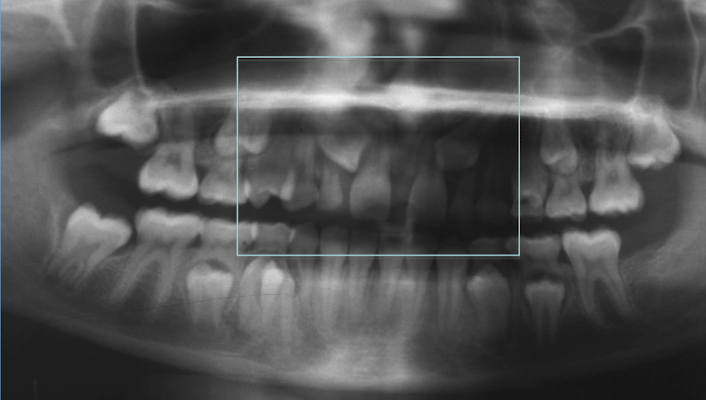

Tx option for this case:

- absent U2s

- ectopic canines

- midline diastema

A

1. extraction URb, ULb

2. sectional fixed appliance to close space between UR1 and UL1

3. allows eruption UR3 and UL3